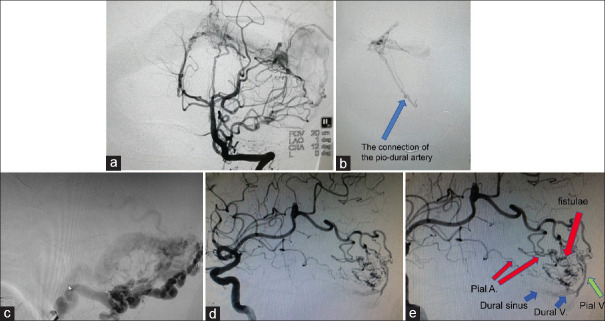

颅内硬脑膜动静脉瘘(DAVF)是一种相对复杂的颅内疾病,其临床表现和治疗策略往往因各种因素而存在很大差异。虽然目前颅内硬脑膜动静脉瘘的治愈率较高,但人们对其病因和发病机制仍缺乏了解。对于颅内动脉相关 DAVF 的治疗策略一直存在争议,对其发病机制也缺乏了解。作者对伴有桡动脉供血的 DAVF 进行了简要的文献综述,并介绍了其所在医疗中心的一些治疗经验。未来的大规模回顾性队列研究和前瞻性研究有望解决这些问题。

Intracranial dural arteriovenous fistula (DAVF) is a relatively complex intracranial condition, and its clinical presentation and treatment strategies often vary significantly due to various factors. Although the cure rate of intracranial DAVF is currently high, there is still a lack of understanding of its etiology and pathogenesis. There is ongoing controversy regarding the treatment strategies for DAVF associated with the pial arteries, and there is a lack of understanding of its pathogenesis. The author conducted a brief literature review on DAVF with pial arterial supply and presented some treatment experiences from their own medical center. Large-scale retrospective cohort studies and prospective research in future are expected to address these issues.